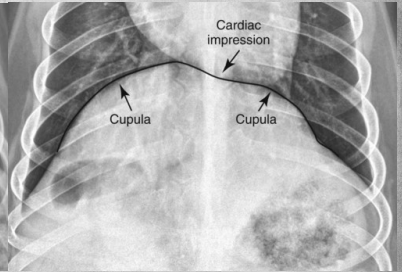

What view is this?

A

left lat

Q

right lat